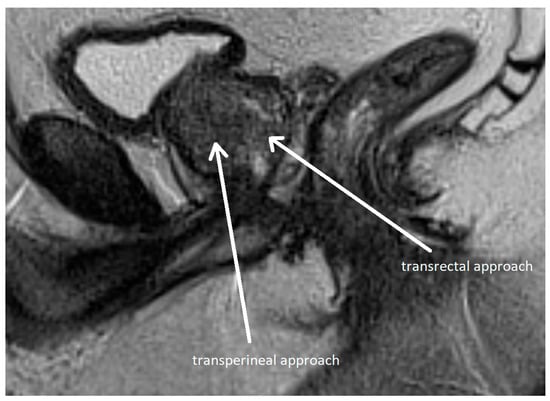

Methods of prostate biopsy can be divided by anatomic access into transrectal and transperineal (see Figure 6). Transperineal access is associated with a lower risk of infectious and hemorrhagic complications and better detection of anterior neoplastic lesions, although the procedure is more painful [115,116,117]. Therefore, the EAU recommends transperineal access as the preferred approach [30]. Biopsy techniques are classified as systematic or targeted, with the latter directed at mpMRI-identified lesions.

Figure 6.

Transperineal and transrectal access routes for prostate biopsy visualized on sagittal multiparametric magnetic resonance imaging (mpMRI). The image illustrates needle trajectories through the perineum (transperineal approach) and rectum (transrectal approach) directed toward the prostate gland. The transrectal route is commonly used due to its simplicity and familiarity but carries a higher risk of infection. In contrast, the transperineal approach provides improved access to anterior and apical zones of the prostate and has a lower risk of sepsis. Adapted from the authors’ own materials, based on Chang et al. [118].